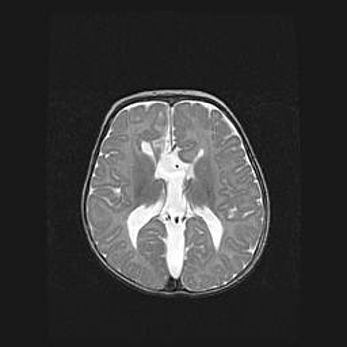

Множественные кисты обоих полушарий головного мозга, наибольшая из них в правой затылочной области. Ассиметричная атрофическая гидроцефалия.

Возраст: 7 месяцев

Вес: 5660 г

Пол: мужской

Окружность головы: 41,5 см

Срок гестации: 28-29 недель

Кисты головного мозга развиваются в результате многоочаговых некрозов вещества мозга и возникают вследствие перенесенной перинатальной инфекции, менингитов, энцефалитов, асфиксии, родовой травмы, расстройств мозгового кровообращения различного генеза. Образованию кист в веществе головного мозга плодов и новорожденных способствуют такие факторы, как высокое содержание в нем воды, недостаточная (или отсутствие) миелинизация и слабая астроглиальная реакция на повреждение.

Кисты могут сочетаться с гидроцефалией и другими поражениями головного мозга.